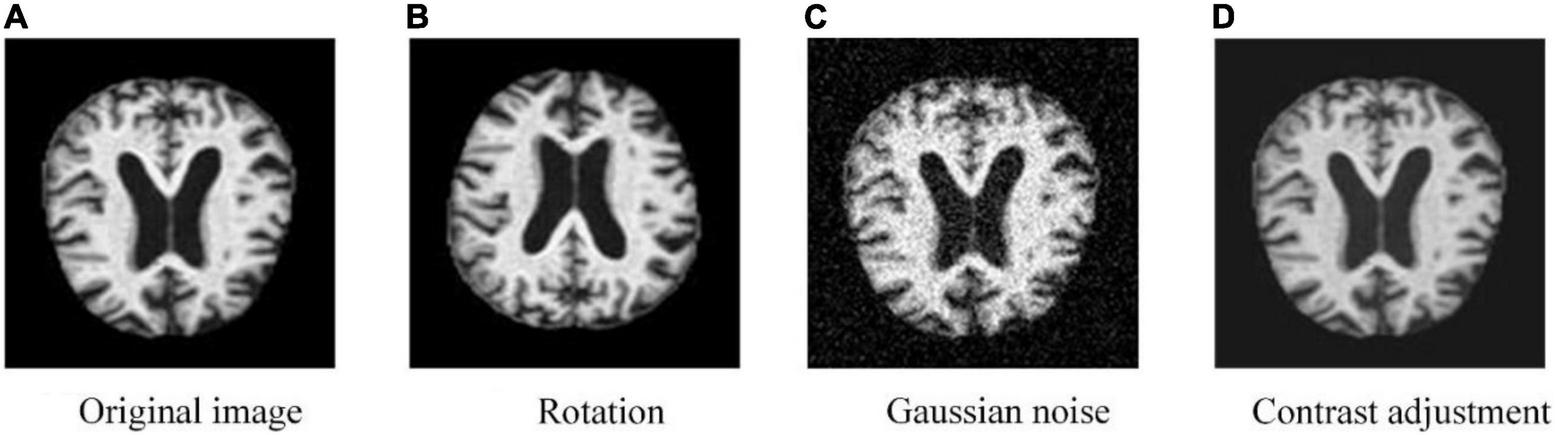

To deal with the problem of classification imbalance in the dataset, the most basic approach is either to directly copy the minority classes and add them to the sample set or to employ a certain percentage of the majority classes as the training set to obtain a relatively balanced dataset (López et al., 2013; Maxwell et al., 2018). However, this approach tends to lead to the problem of model overfitting, which makes the information learned by the model not generalized enough. To address this problem, Chawla et al. (2002) proposed the Synthetic Minority Oversampling Technique (SMOTE), which uses the similarity between the classes with fewer samples in the feature space to build synthetic new samples and add them to the minority classes. The SMOTE is a good solution to the problem that the information obtained by random oversampling is too special and not generalized enough. Therefore, we combine SMOTE with data expansion (flipping, adding random Gaussian noise, and contrast adjustment) for Alzheimer’s disease to perform class-balancing preprocessing for better training results.

(1) To solve the problem of classification imbalance in the Alzheimer’s disease dataset, we increased the data volume in the minority classes using data expansion methods such as flipping, adding noise, and contrast adjustment (as depicted in Figure 1), and performed class-balancing operation using SMOTE (the results are displayed in Table 1). SMOTE performs a class-balancing operation by artificially synthesizing new samples from the minority classes and adding them to the dataset for classification balance, which well solves the problem of model overfitting, as displayed in Table 2. In the MPC-STANet model, the recognition accuracy of the class-balancing processed dataset is improved by 10.7% compared to the unprocessed dataset.

Training the neural network model with more datasets allows it to learn more effective feature points to improve the recognition accuracy of the model, prevent overfitting, etc. We use MATLAB 2020b to flip the image, add random Gaussian noise, contrast adjustment, and other data expansion methods to expand the minority classes to improve the training effect of the neural network model. Also, the data expansion method is an important way to balance the data volume of different classes and the result images are shown in Figure 4.